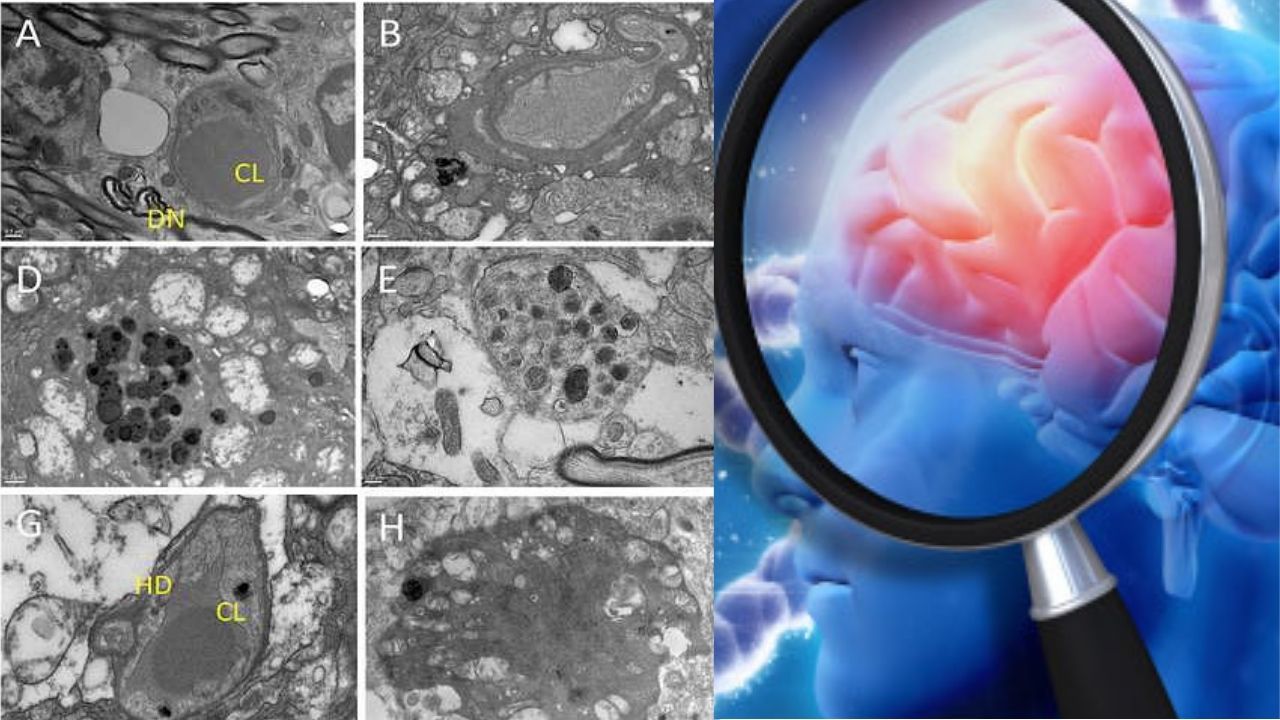

What Causes Alzheimer’s Disease? Scientists May Have Finally Discovered It

For years, scientists have been studying how the accumulation of toxic molecules in the brain could cause or…